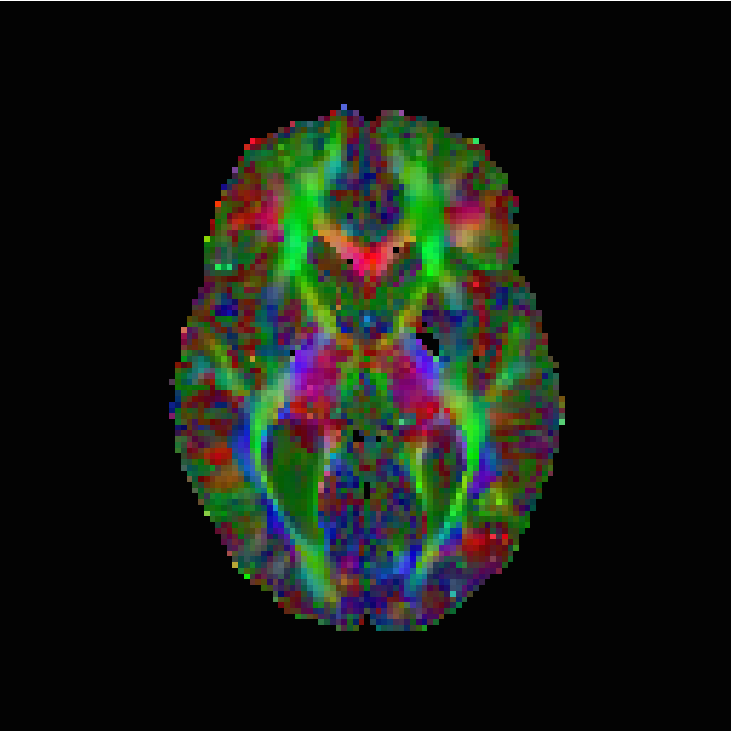

We now wish to study the proposed regularisation model on a real in-vivo diffusion tensor image. Our data is that of a human brain, with the measurements of a volunteer performed on a clinical 3T system (Siemens Magnetom TIM Trio, Erlangen, Germany), with a 32 channel head coil. A 2D diffusion weighted single shot EPI sequence with diffusion sensitising gradients applied in 12 independent directions (). An additional reference scan without diffusion was used with the parameters: , , flip angle . Each slice of the 3D data set has plane resolution , with a total of pixels. The total number of slices is 60 with a slice thickness of 2mm. The data set consists of 4 repeated measurements. The GRAPPA acceleration factor is 2. Prior to the reconstruction of the diffusion tensor, eddy current correction was performed with FSL [47]. Written informed consent was obtained from the volunteer before the examination.

The results are in Table 2 and Figures 6–8, again with the first of the figures showing the colour-coded principal eigenvector of the reconstruction, the second showing the fractional anisotropy and principal eigenvectors, and the last one the errors in the latter two, in a colour-coded manner. Again, all plots are masked to represent only the non-zero region. In the figures, we concentrate on error bounds based on 95% confidence intervals, as the results for the 90% and 99% cases do not differ significantly according to Table 2.

This time, the linear approach (3.3) has best overall reconstruction (Frobenius PSNR), while the nonlinear approach (3.2) has clearly the best principal eigenvector angle reconstruction besides the regression, which does not seem entirely reliable regarding our regression-based pseudo-ground-truth. The constraints based approach (3.5), with 95% confidence intervals is, however, not far behind in terms of numbers. More detailed study of the corpus callosum in Figure 8 (small picture in picture) and Figure 7 however indicates a better reconstruction of this important region by the nonlinear approach. The constrained approach has some very short vectors there in the white region. Naturally, however, these results on the in vivo data should be taken with a grain of salt, as we have only a somewhat unreliable pseudo-ground-truth available for comparison purposes.